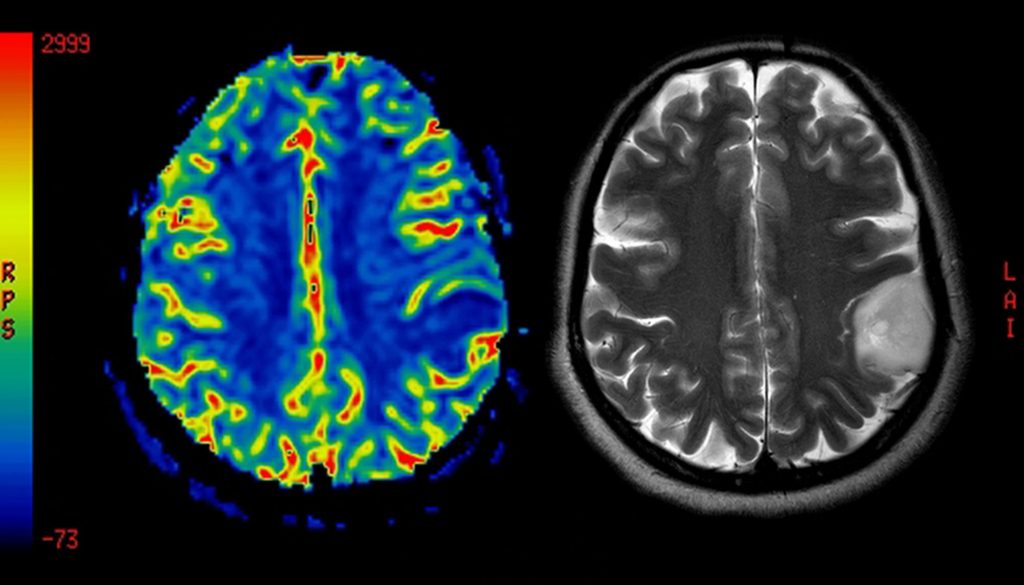

1. **الفحوصات الطبية**:

تأكد من إجراء جميع الفحوصات اللازمة مثل الرنين المغناطيسي أو الأشعة المقطعية.

1. **الفحوصات الدورية**:

مثل الرنين المغناطيسي لمراقبة التطورات.